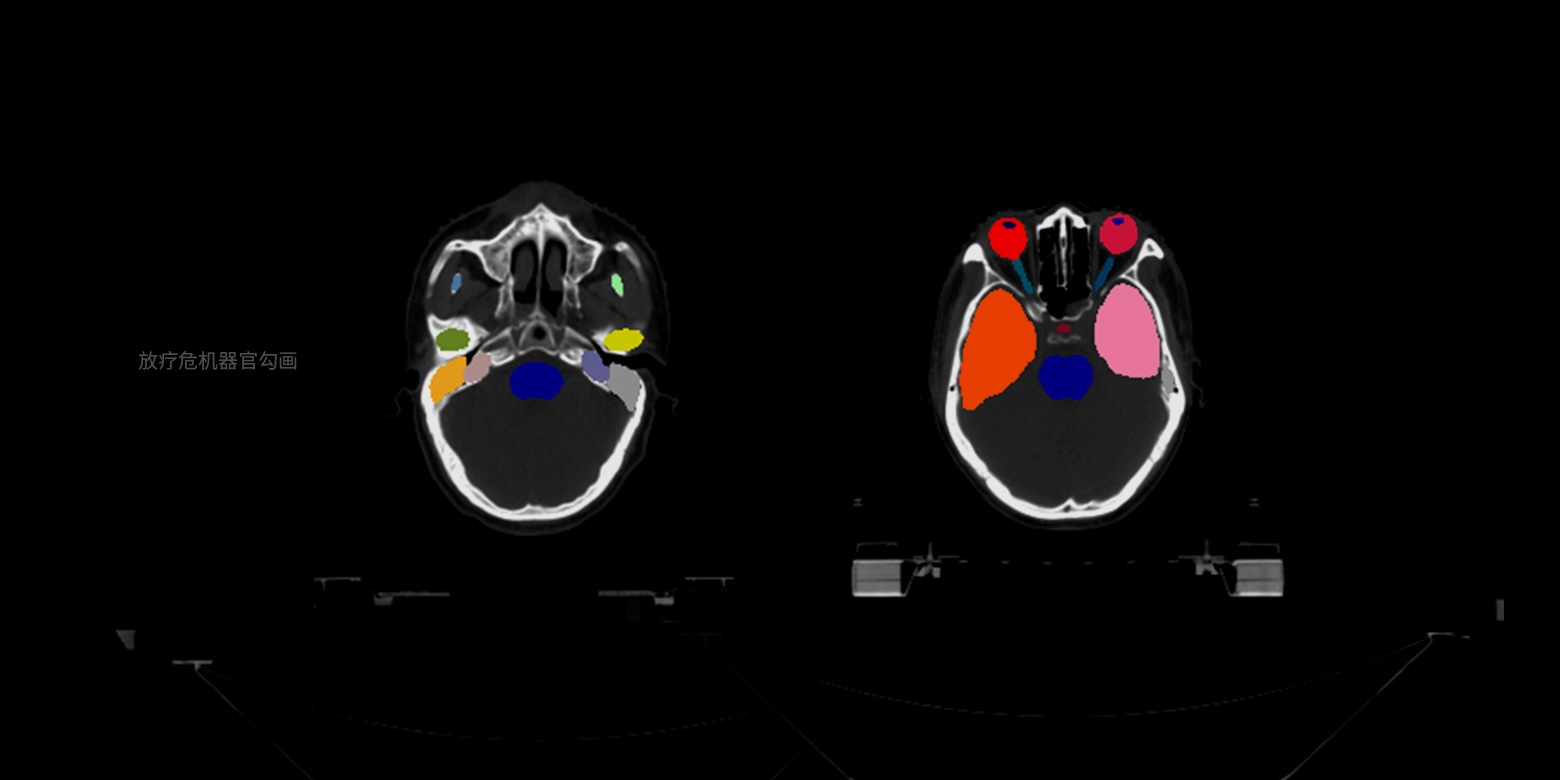

病灶/部位分割与量化

支持基于小样本精细医学数据标注进行训练,实现多种病灶、器官等的像素级精确边界分割,并自动进行关键信息的量化分析,例如放疗靶区勾画、骨盆肿瘤分割等,将医生从耗时耗力的人工手动勾画中解放,满足量化诊断、手术个性化规划等场景的需求。